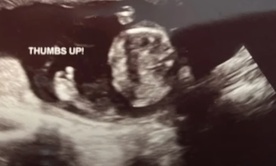

Nienarodzone dziecko podniosło kciuk do góry - i to w najlepszym momencie

Nienarodzone dziecko podniosło kciuk do góry - i to w najlepszym momencie Good luck! lifenews.com/Pregnancy Center East

Minionej jesieni do Pregnancy Center East zgłosiła się matka, która chciała zobaczyć swe dziecko na USG. Była ostatnią pacjentką tego dosyć trudnego dnia. Gdy wykonująca badanie Lauren Purtee najechała głowica na dłoń maleństwa, na ekranie pojawił się jego kciuk uniesiony w górę w dobrze znanym, choć oczywiście nieświadomym geście. Wszyscy w pokoju roześmiali się serdecznie.

Ta sytuacja natchnęła obrońców życia z Cincinnati otuchą.